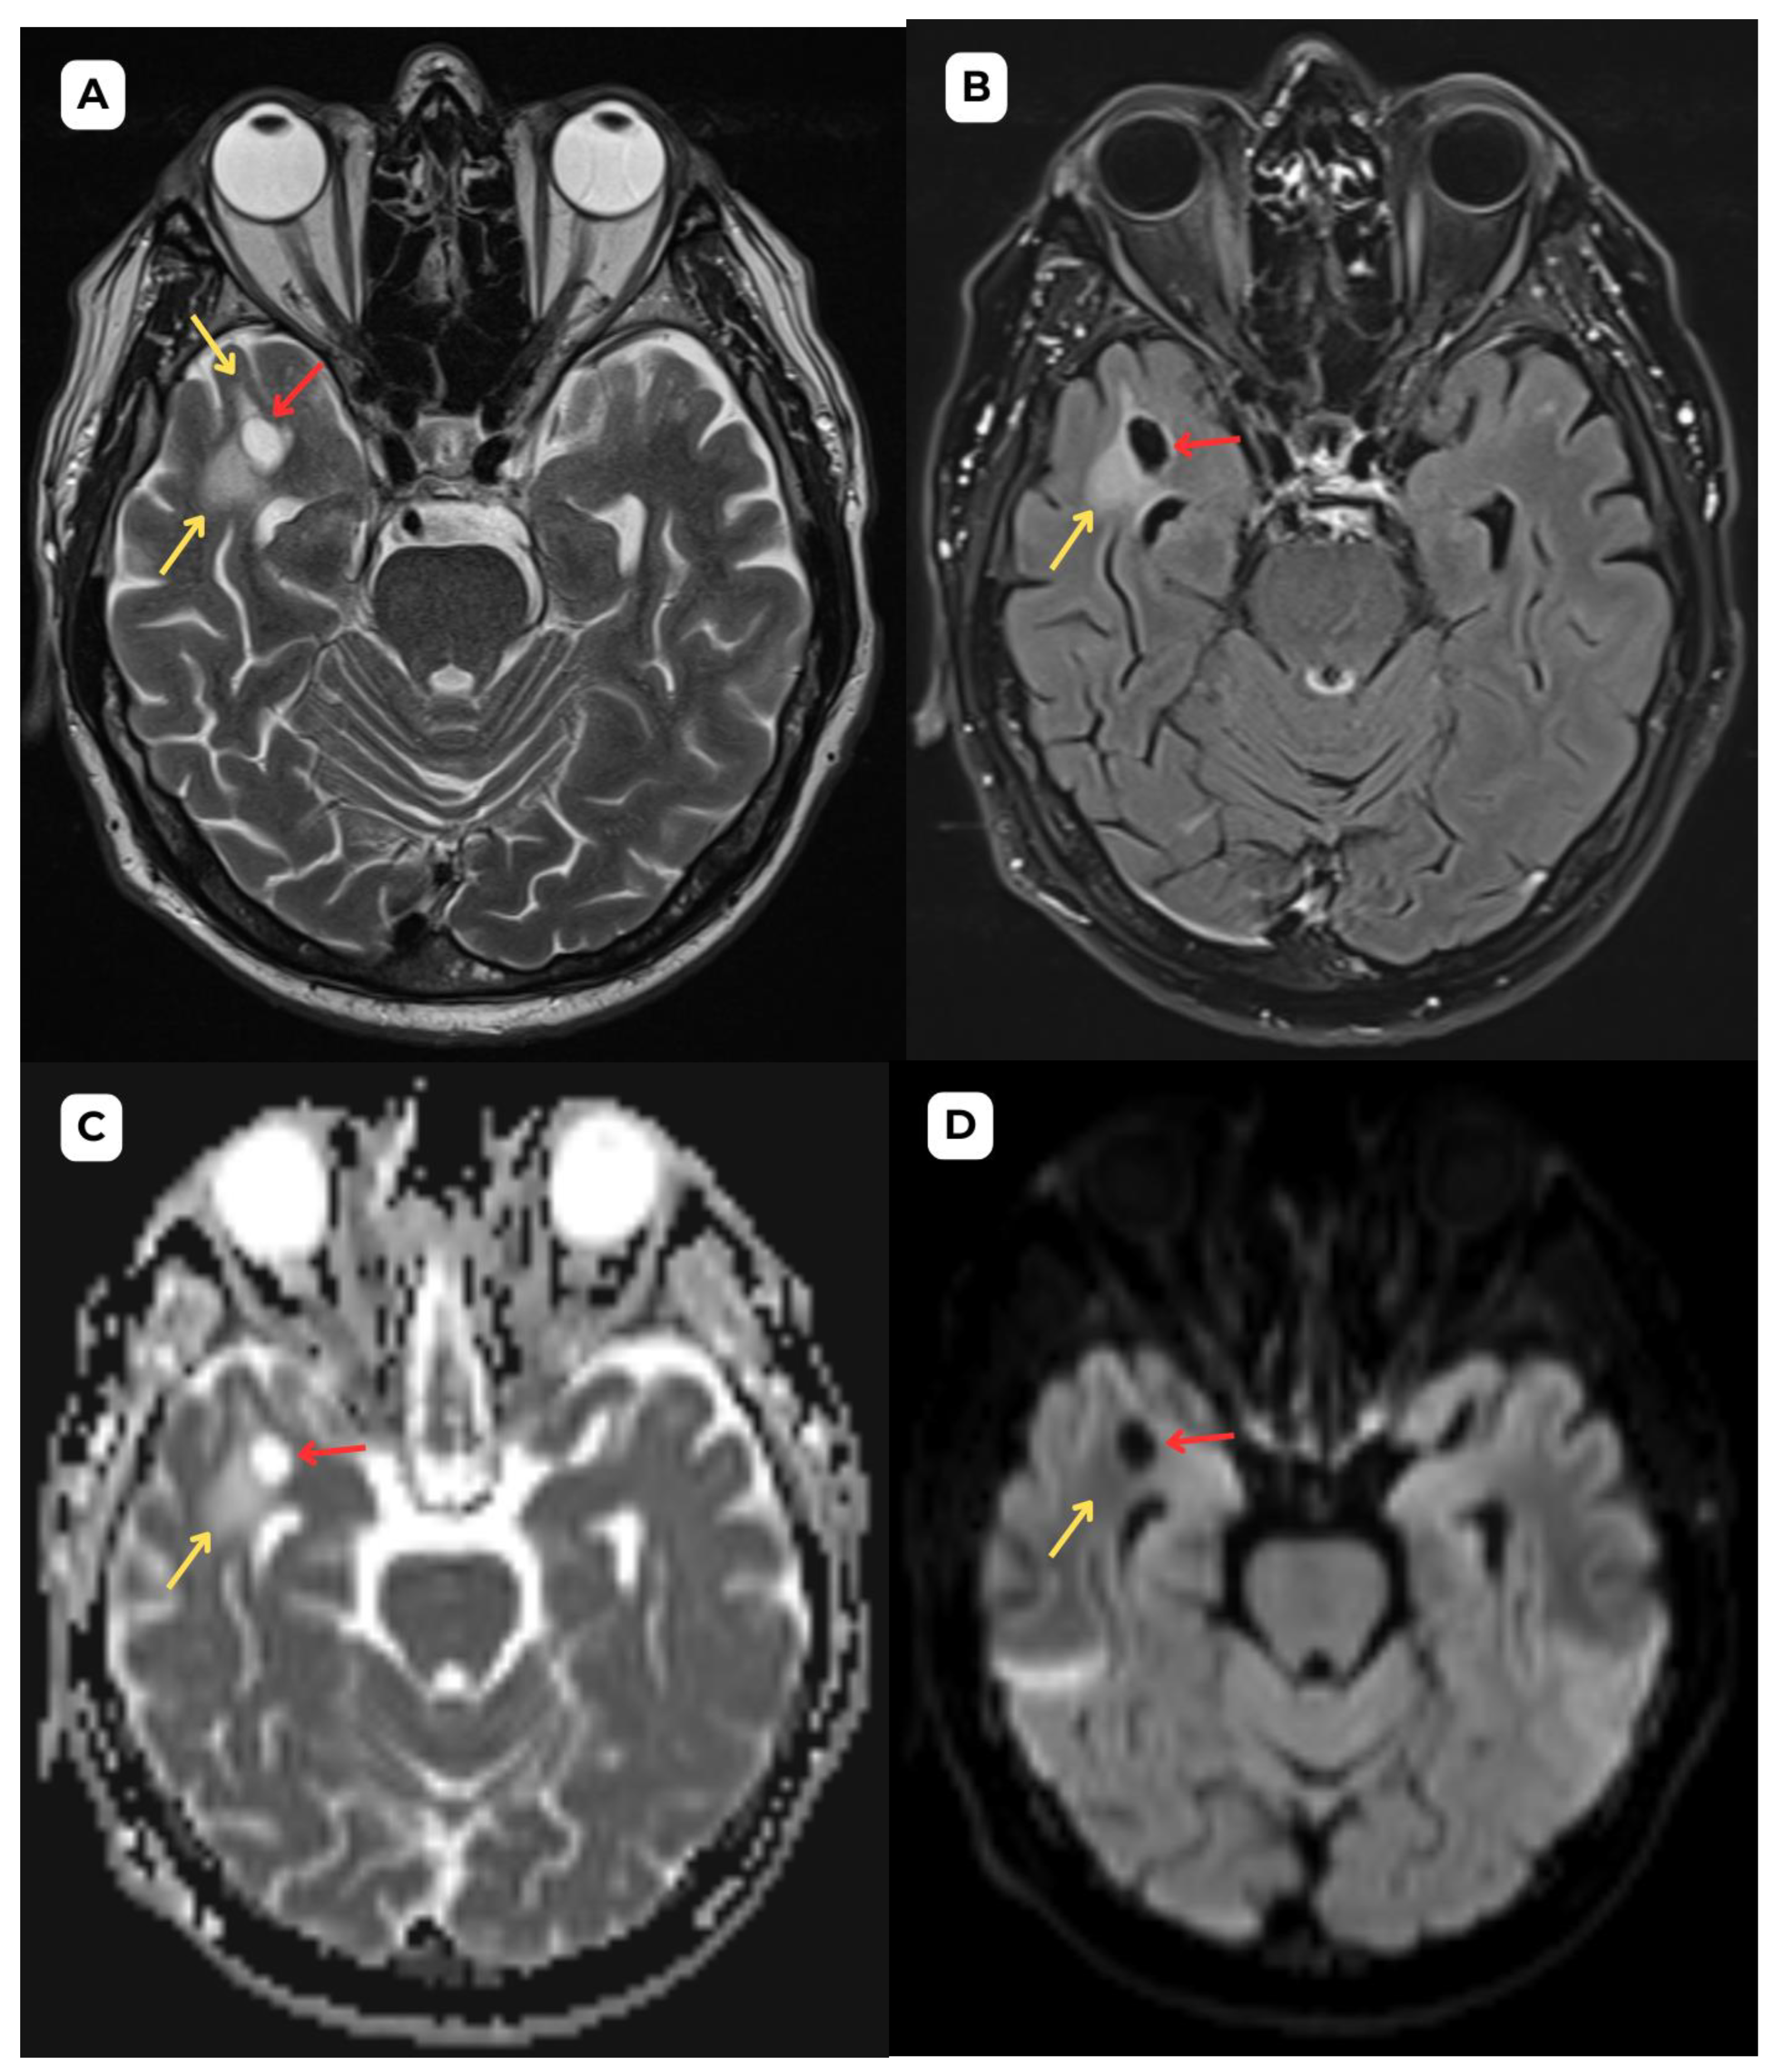

Figure 3. First patient: One-year follow-up brain MRI of a 63-year-old male. (A): T2-weighted sequence axial and (B): T2-weighted sequence axial zoomed in. One-year follow-up shows no changes in the cystic lesion or surrounding structures, supporting the diagnosis of a benign process, consistent with an opercular perivascular space (type IV). The surrounding edema seen previously has remained stable, with no increase in size or signal intensity, further suggesting a non-progressive, benign nature of the lesion. One-year follow-up shows no changes in (C): high ADC map values and (D): no diffusion restriction on DWI B1000. Red arrow—opercular (type IV) perivascular space, yellow arrow—surrounding edema.

The stability of the lesion and surrounding tissue over the one-year period is reassuring. However, the need for continued monitoring in such cases remains a subject of discussion, as some studies suggest that these lesions tend to remain stable and do not require further follow-up unless there are significant changes [1]. For example, in a study by McArdle et al., 18 patients with opercular perivascular cysts were analyzed. Of the 13 patients who underwent follow-up over a period ranging from 2 months to 10 years, 11 showed no change in cyst size, and only one patient demonstrated a slight increase over a 7-month period [1]. These findings support the notion of long-term structural stability. Additionally, sources such as Radiopaedia.org highlight that opercular (type IV) perivascular spaces, when presenting with typical features, are considered benign and often do not require further imaging unless clinical symptoms or atypical imaging features are present.

On the other hand, several authors suggest that such lesions, once identified correctly, typically require only follow-up imaging for monitoring [11,12]. Contrary to the generally stable nature of enlarged perivascular spaces over time, serial MRI studies show a prolonged increase in the size of low-grade neuroglial tumors, averaging 4.1 mm per year [13]. In this case, the aforementioned changes have remained stable over a one-year follow-up MRI.